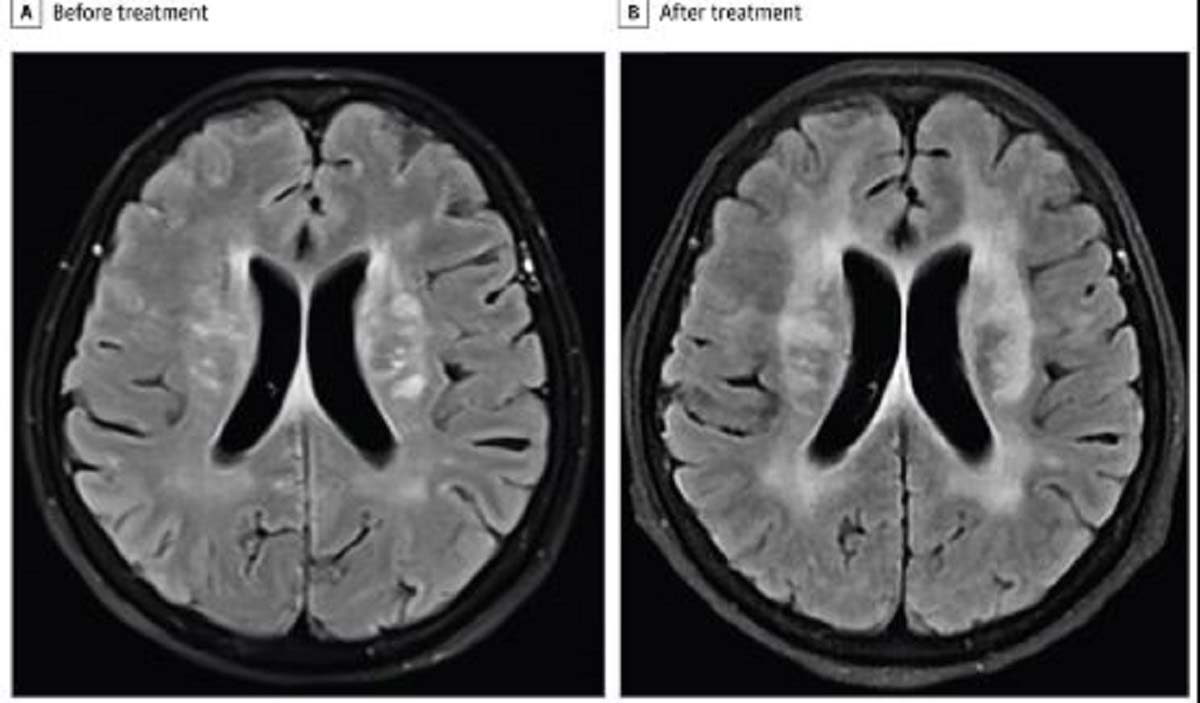

중국 광저우 의대 의료진에 따르면, 60세 여성은 발열과 함께 정신 혼란 증상을 겪었다. 증상은 3일 정도 지속됐고, 대화도 제대로 하지 못했다. 이후 이 여성은 병원을 찾았고, 의사는 CT 검사 결과 뇌수막염을 의심했다. 이후 2주간 항생제를 투여했다. 하지만, 그의 증상은 호전되지 않았다. 추가 MRI 검사에서는 뇌의 백질 병변이 더 심해진 것을 확인했고, 혈액 검사에서 호산구 수치가 비정상적으로 높은 것을 발견했다. 의사는 기생충 감염을 의심했고, 결국 여성은 호산구성 수막염(뇌와 척수를 감싸는 얇은 막인 수막에서 염증이 생기는 질환)을 진단받았다. 호산구는 백혈구의 한 종류로, 기생충 감염 시 증가하는 면역 세포다. 알고 보니 여성이 덜 익은 가재를 먹은 후 광동주혈선충이라는 기생충에 감염됐던 것이다. 여성은 즉시 벌레 감염을 치료하는 구충제인 알벤다졸을 투여 받았고, 2주 만에 다시 의사소통이 가능해졌다. 4개월 후 그는 추가 뇌 스캔 결과, 건강이 거의 다 회복한 것으로 나타났다.